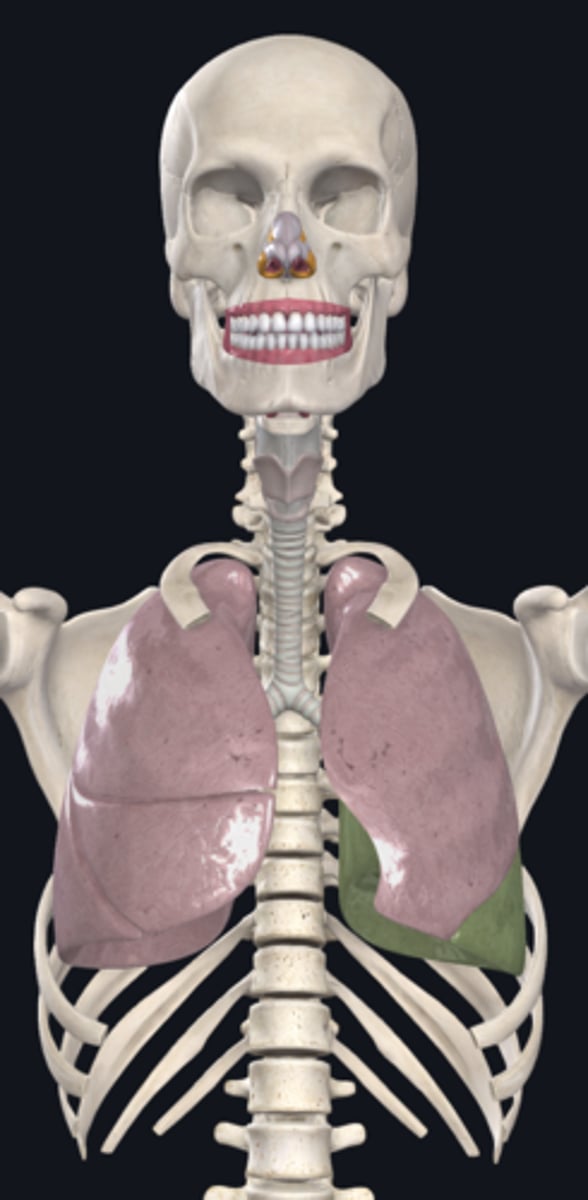

right lung

superior lobe of right lung

middle lobe of right lung

inferior lobe of right lung

left lung

superior lobe of left lung

inferior lobe of left lung

base (diaphragmatic surface)

apex

diaphragm